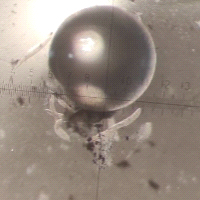

Перед вами фотография среза мышечной ткани собаки, которая страдала паразитарным заболеванием — гепатозоонозом. На срезе видны многочисленные мышечные волокна (розового цвета с фиолетовыми ядрами) и многослойное округлое образование, расположенное в самом центре. Это циста, внутри которой развивается возбудитель болезни — одноклеточный паразит Hepatozoon americanum из группы споровиков (Apicomplexa), к которой относятся также всем известные токсоплазма и малярийный плазмодий.

Паразиты активно проникают внутрь макрофагов (с помощью апикального комплекса органелл) и начинают формировать ту самую цисту, которую вы видите на фотографии. В самом ее центре находится «плененный» макрофаг, у которого хорошо заметно смещенное к краю ядро с ядрышком. Но где же сам гепатозоон? Паразит занимает весь остальной объем клетки макрофага, потеснив его ядро к периферии. На фотографии видна стадия развития гепатозоона, когда он только приступает к внутриклеточному размножению (стадия шизонта): его ядро уже многократно поделилось, но еще не произошло образование оболочек клеток вокруг дочерних ядер. Поэтому на фото нельзя различить отдельные клетки гепатозоона внутри макрофага. Зато хорошо заметна многослойная оболочка цисты, которая дала этой структуре название циста-«луковица» (onion skin cyst). Гепатозоон вызывает в макрофаге усиленный синтез мукополисахаридов, которые слоями откладываются на поверхности клетки, делая ее похожей на луковицу. Предположительно, такая многослойная циста защищает гепатозоон от иммунной системы хозяина, что необходимо на этой стадии. Цисты-«луковицы» имеют размер от 80 до более чем 300 мкм.

Развитие H. americanum в скелетных мышцах. A — «циста-луковица» (O): содержит клетку хозяина с ядром (показано короткой стрелкой) и большим ядрышком. В клетке хорошо заметен трофозоит (показан длинной стрелкой). Многослойная оболочка цисты состоит из мукополисахаридов, синтезированных инфицированной клеткой хозяина. B — ранний этап развития шизонта (показан короткими стрелками). C — шизонт с хорошо дифференцированными мерозоитами. D — гранулёма — скопление макрофагов в очаге воспаления, многие с паразитами внутри (показаны короткими стрелками). Длина масштабного отрезка: 50 мкм (A и D), 25 мкм (B и C). Фото из статьи S. A. Ewing, R. J. Panciera, 2003. American Canine Hepatozoonosis